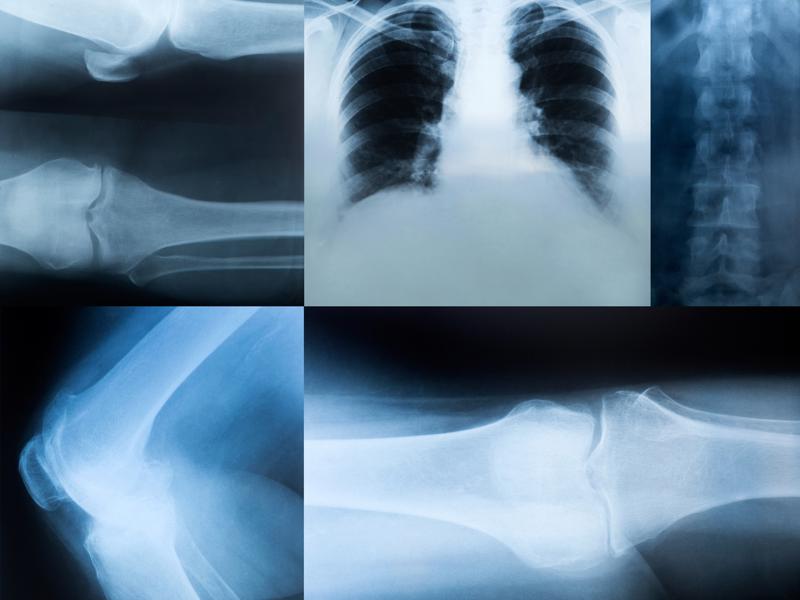

X-Ray & Fracture Care

With an in-house X-ray machine, Dr. Ward is able to quickly review images to diagnose minor trauma injuries like fractures and broken bones.

As you may know, an X-ray machine uses electromagnetic radiation to take pictures of a patient’s bones or other internal structures. X-ray images are recorded either on film or recorded digitally. Bones appear white on the images because they block particles that are electromagnetically emitted by the X-ray machine. Muscle and fat, however, appear with a grayish hue. Dr. Ward reviews the X-ray image to determine if a bone is broken or fractured.